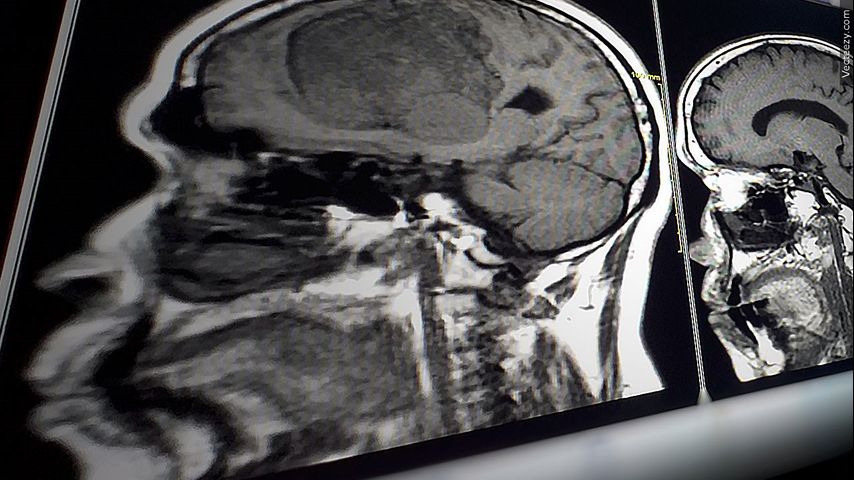

BATON ROUGE — Damaged blood vessels can deprive your brain of vital oxygen and nutrients, which could lead to a condition called vascular dementia.

"It's affecting the cables that connect the brain cells. And so our brains are working not at full speed,” Mayo Clinic neurologist Stephen English said.

English says the signs of vascular dementia include problems with reasoning, planning, judgment, memory and other thought processes.

Factors that increase the risk of heart disease and stroke also raise vascular dementia risk.

"High blood pressure, high cholesterol, diabetes, smoking, sleep apnea — these are the modifiable risk factors that, if untreated, can cause wear and tear on the small blood vessels in the brain over time,” English said.